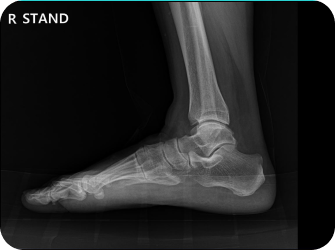

척추 엑스레이 검사

족부 엑스레이 검사